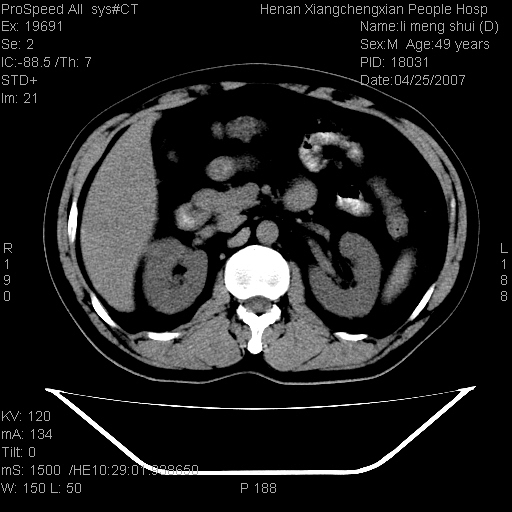

| 患者,男,49岁, 腹疼伴恶心\\呕吐20天,20天前无明显诱因出现右上腹部疼痛,钝疼,无放射,伴恶心\\呕吐,不伴发热.患者不愿增强. b超:肝脏右叶实性占位. ct:肝脏右叶可见一巨块状圆形低密度影,大小约93mm*84mm,其内可见点状高密度影,胆囊、胰腺、脾脏大小、形态及密度未见异常,腹膜后间隙未见肿大淋巴结影。 印象:肝脏右叶巨大肿块,性质待定,建议增强并穿刺活检进一步确诊。 ct平扫: ![]() ![]() ![]() ![]() ![]() ![]() ![]() ![]() ![]() ![]() ![]() ![]() ![]() ![]() ![]() ![]() ![]() 肝脏右叶肿块ct引导下穿刺活检术 患者于16时05分仰卧于ct检查台上,首先行肝脏ct扫描确定进针位置、深度、角度。在局麻下行ct引导下肝脏右叶肿块穿刺活检术。常规消毒、铺巾、局麻。在ct引导下使活检针经右侧腋中线、第9肋间隙垂直胸壁进针90mm,针头进入病变预定位置。在病变预定位置多点、多方向抽取小米样病变组织多块,涂片五张送病理检查。术后穿刺点局部无出血,未出现腹腔积液等并发症。术中及术后患者生命体征稳定,手术于17时10分成功完成。患者安返病房。 穿刺片 ![]() ![]() ![]() ![]() ![]() ![]() ![]() ![]() ![]() ![]() ![]() ![]() ![]() ![]() ![]() ![]() 病理结果肝细胞癌 ![]() 原贴地址:http://www.radinet.com.cn/forum_view.asp?forum_id=4&view_id=24130 ok |